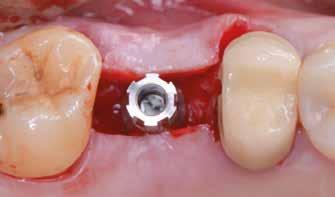

1. ábra: Műtét előtti fogászati panorámafelvétel, amelyen a hiányzó felső állcsont jobb első premolárisát és a szabad véggel rendelkező hidat láthatjuk. — 2. ábra: Az implantátum méreteinek megtervezése CBCT-vel. 3. ábra: Bukkális lágyrészdefektus. — 4. ábra: A biológiai szélesség értékelése a vertikális lágyszövetvastagság alapján. 5. ábra: Palatinális „tekercslebeny” – Palatal roll flap. — 6. ábra: Bredent medical copaSKY 4x10 implantátumbeültetés. 7. ábra: Szubkresztális implantátumbeültetés a várható biológiai szélességnek megfelelően.

Sebészeti eljárás

Az eljárást helyi érzéstelenítés mellett végeztük (4%-os articaine-hidroklorid 1:100 000 adrenalinnal). Papillakímélő, U alakú palatális bemetszést végeztünk, teljes vastagságú nyálkahártyalebeny preparálás történt, a lebenyt bukkálisan feltekertük (5. ábra). A lebeny bukkálisan feltekert részén de-epitelizációt végeztük el, amellyel kompenzálni tudtuk a bukkális lágyszöveti defektust. Szakaszos előfúrást végeztünk, és a bredent copaSKY 4x10 implantátumot 30 Ncm behajtási nyomatékkal helyeztük be (6. ábra). Az implantátumot 1 mm-re szubkresztálisan helyeztük be, hogy később szélesebb emergenciaprofilt tudjunk kialakítani (7. ábra). Az egyedi ínyformázó úgy készült, hogy kompozitot vittünk fel a titánbázisra, és így formáztuk a lágyszöveteket a transzgingivális gyógyulási fázis során (8. ábra). Az egyéni ínyformázó tulipán formájú, hogy kialakítsa a kívánt emergenciaprofilt. A lágyszövetet feszülésmentesen zártuk #6/0 nem felszívódó, monofil fonallal (Optilene, B. Braun Deutschland; 9. a–b. ábra). Posztoperatív röntgenfelvétel készült, ami alapján az implantátum a szomszédos fogakkal párhuzamos elhelyezést mutatott (10. ábra). Posztoperatív utasításokat adtunk a páciensnek a műtéti terület körüli szájhigiénia fenntartása érdekében. A beavatkozást követő egy héttel a varratokat eltávolítottuk, és a kezelt terület kielégítő gyógyulást mutatott (11. ábra). A 4 hónap utáni késleltetett terhelést a páciens kívánsága szerint terveztük.